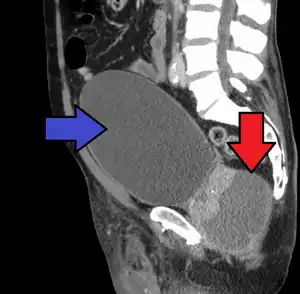

| CT scan showing an abscess of the prostate (red arrow) resulting in urinary retention (blue arrow) | |

The diagnosis should be suspected in someone who has acute prostatitis that is not improving and can be confirmed by medical imaging.[1] The preferred method of imaging is generally ultrasound of the prostate via the rectum.[1] CT scan of the abdomen and pelvis may be less painful.[1] MRI may also be useful in certain cases.[1]